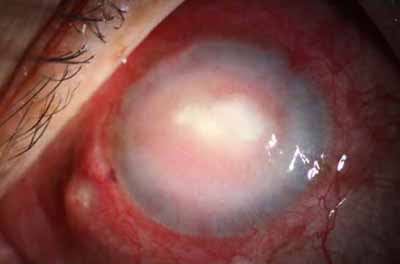

En su evolución se observará aumento del edema, aparición de un anillo inmunológico (Wessely), agrandamiento y coalescencia de los infiltrados que progresan hacia la formación de un absceso, queratolisis superficial, adelgazamiento y perforación corneal.

La vascularización y el hipopion son poco frecuentes en los estadios tempranos de la queratitis. Con el tiempo, en los estados avanzados de invasión estromal, aparecen vasos estromales

Ínício síntomas 6 meses - evolución catastrófica

Evolución Complicada

Início síntomas 60 dias - No PL